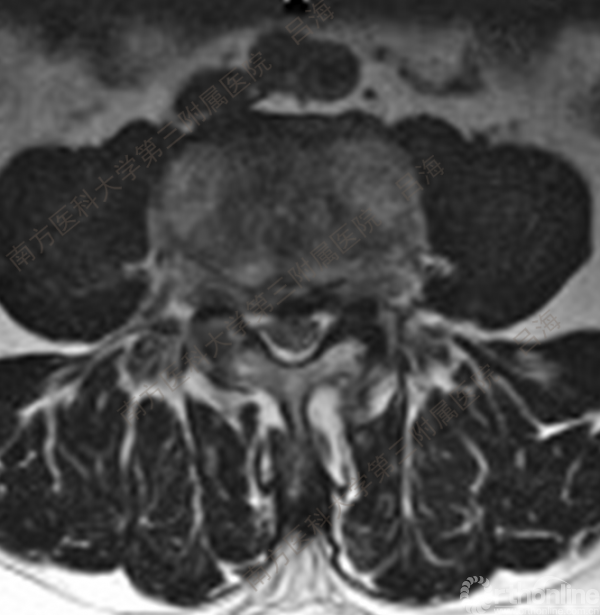

随着社会老龄化进程加快,胸腰椎退行性病变的治疗已经成为脊柱学术界的一个热点话题。MIS-TLIF手术可以治疗多种不同的胸腰椎退行性疾病,南方医科大学第三附属医院吕海教授结合病例为我们一一展示了该术式在治疗不同胸腰椎疾病时的具体手术过程。